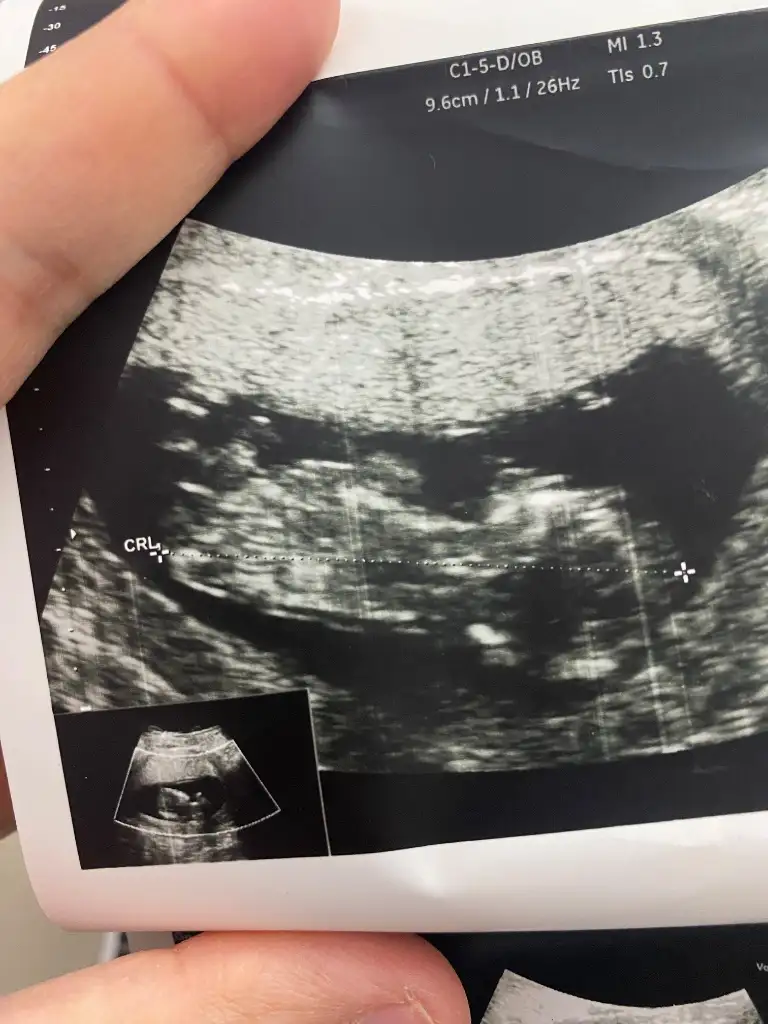

13. Haftaya yeni girdik tahmininiz nedir acaba?

• c45671b1-548e-44e6-85d4-cf0b1aea9f9f.webp

c45671b1-548e-44e6-85d4-cf0b1aea9f9f.webp

19 KB · Görüntüleme: 238